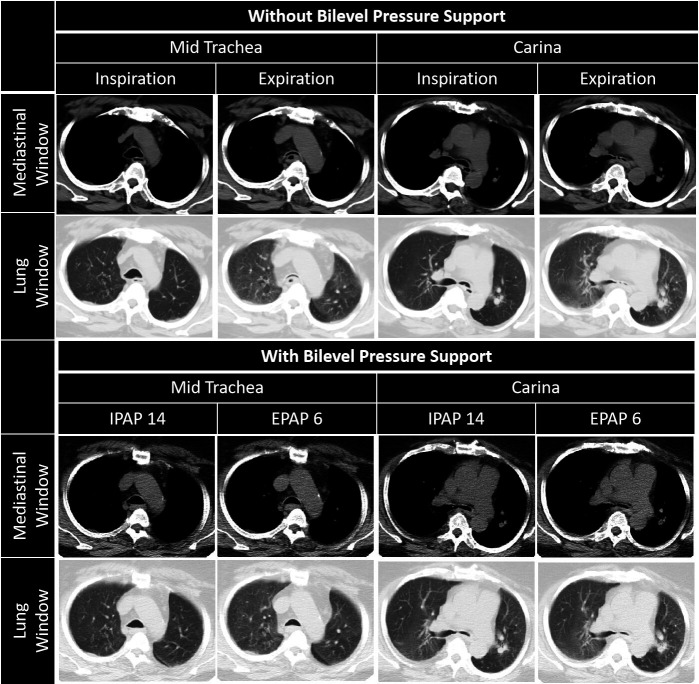

Figure 2.

Dynamic CT images of thorax off (top two rows) and on (bottom two rows) bilevel positive airway pressure support (BPAP). Top two rows: when off BPAP, complete collapse of trachea and left main bronchus, and narrowing of right main bronchus, associated with bilateral air trapping (lung window) is seen during expiration. Bottom two rows: with expiratory positive airway pressure (EPAP) of 6 cm H2O, the observed luminal patency in trachea and left main bronchus, is less than that which is achieved with an inspiratory positive airway pressure of 14 cm H2O during inspiration. Though the luminal opening of left main bronchus achieved by the lower EPAP is not satisfactory radiologically, it appears sufficient enough and ensures effective ventilation, as shown on dynamic real time imaging, as well as by measured consistent clinical improvement.